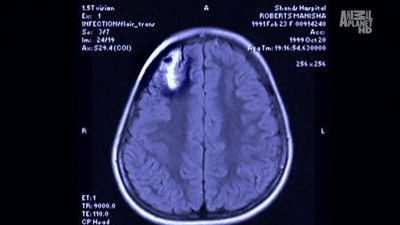

A nine-year-old hockey player comes down with encephalitis from the Acanthamoeba, which causes him to lose his concentration and balance, almost killing him. A computer programmer gets severe malaria from the Plasmodium parasite that makes him lose control of his mind and post-malarial neurological symptoms two weeks after an apparent recovery. A marathon runner deals with Leishmaniasis, which causes his spleen to swell.